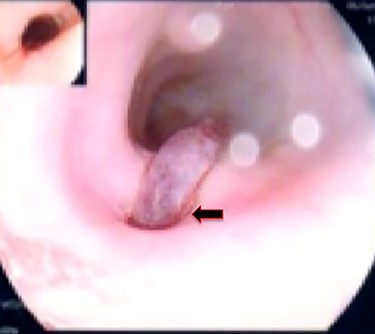

A 36-year-old male, involved in a minor motor vehicle accident while driving his car. He lost consciousness following a sudden onset of transient loss of vision which was not associated with palpitation or dizziness. His previous medical history revealed arterial hypertension and a corrected aortic coarctation with interposition graft at the age of 14. Pan CT scan was unremarkable except for thickening of the desending throacic aorta. His white blood count was very high (68 000 per cubic millimeter of blood). One day after the car accident, he developed nausea, hematemesis and melana. Upper GI endoscopy revealed blood in the stomach and distal esophafgus with no identifiable source of bleeding (Fig. 6). The patient developed massive hematemsis with hypotension requiring intubation and resuscitation. Another CT scan showed air pocket around distal aorta and contrast extravasation to the esophagus (Fig. 7). Another endoscopy revealed distal esophageal ulcer with clot extending toward the stomach (Fig. 8). AEF was suspected and then confirmed by aortogram. The fistula was treated by TEVAR (20 mm × 11.5 cm Valiant covered stent - Medtronic company, USA) followed by fully covered esophageal stent in the middle of the esophagus (Fig. 9).

First upper endoscopy blood within the stomach and duodenum; the esophagus image was not clear and no active bleed can be seen.

Second upper endoscopy fresh bleeding from the distal esophagus and after washing the blood an adherent clot extending from an ulcer going down into the stomach can be seen.